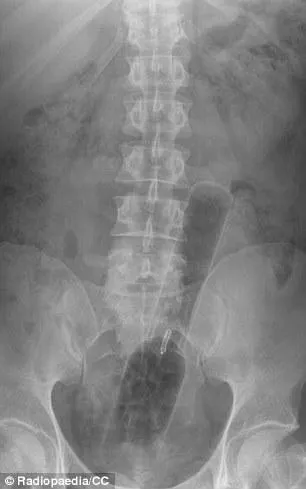

Pas facile de garder son sérieux pour le médecin qui a découvert la silhouette d"une bouteille d"un soda très connu en visionnant la radio du rectum de son patient.